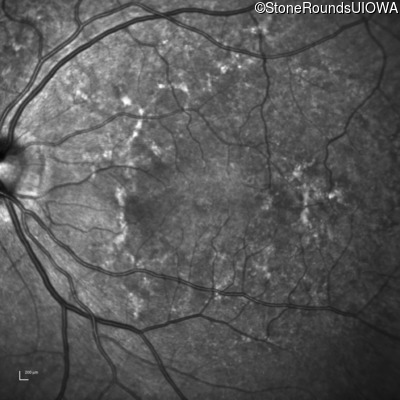

Late Onset Retinal Dystrophy (IIIA3)

Age at visit: 61 years

This 61 year old woman reports some moderate night blindness over the past 10 years.

Diagnosis & molecular findings

Late Onset Retinal Dystrophy C1QTNF5 Ser163Arg AGC>AGA   AD